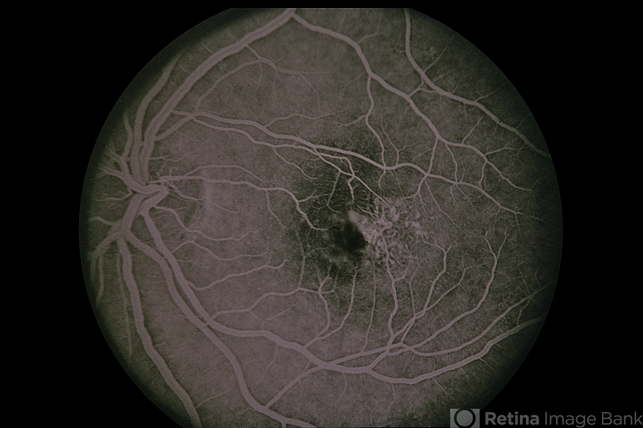

37-year-old female, juxtafoveal telangiectasis / DM / diabetes.

juxtafoveal telangiectasis, diabetes